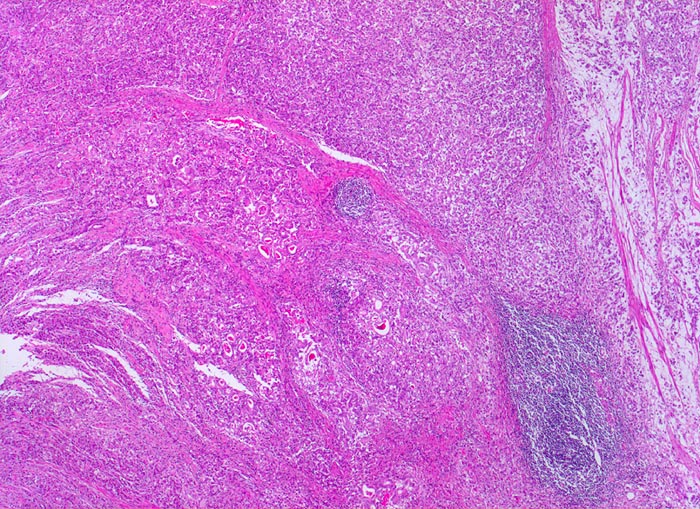

Adenokarzinom des Magens

Das Karzinom breitet sich diffus in der gesamten Magenwand aus. Rechts im Bild sieht man die durch den Tumor aufgesplitterte Muscularis propria.

Diffuse Verdickung und Versteifung der Magenwand im Sinne einer Linitis plastica bei intakter Schleimhautoberfläche. Aufhebung des Faltenreliefs.

Die Magenkarzinome können nach Lauren in einen intestinalen und einen diffusen Typ eingeteilt werden. Karzinome vom intestinalen Typ bestehen aus Karzinomdrüsen, welche einen umschriebenen expansiv wachsenden Tumor bilden. Der diffuse Typ besteht aus Tumorzellen, welche keine Drüsen bilden sondern die Magenwand einzeln oder in kleinen Verbänden diffus infiltrieren. Meist handelt es sich dabei um den histologischen Subtyp von Siegelringkarzinomen. Daneben gibt es auch eine Mischform mit Anteilen vom diffusen und vom intestinalen Typ.